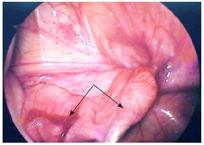

腹阴囊鞘膜积液6例,例3和例6患儿出生后即发现,手术年龄分别为20月、40月。除例6患儿临床诊断腹股沟斜疝外,其余5例临床均诊断精索鞘膜积液。查体可见腹股沟至阴囊区体积大、张力高囊性包块,透光实验阳性(图1)。例3~例6患儿超声提示腹股沟区睾丸后上方低回声包块并延伸至腹腔,积液量多,有时可见分隔(图2)。腹腔镜术中见例6患儿腹腔内囊性包块位于精索后外侧腹膜后,囊膜为腹膜组织,排尽液体后囊膜不能回纳至鞘突管(图3),其余5例患儿囊性包块均自内环口处脱出(图4)。例1和例3患儿先将腹腔内包块还纳至鞘突管,再行鞘状突高位结扎,最后经阴囊抽出积液。其余4例患儿先穿刺针刺破腹腔内囊性包块,将囊液排尽,再囊膜还纳至鞘突管后,行鞘状突高位结扎。例4和例5患儿腹腔内包块液体排尽,高位鞘状突结扎后,仍经阴囊分别抽出15 ml、20 ml液体。所有患儿常规随访,术后3个月复查超声,随访10~24个月,无再次出现症状。